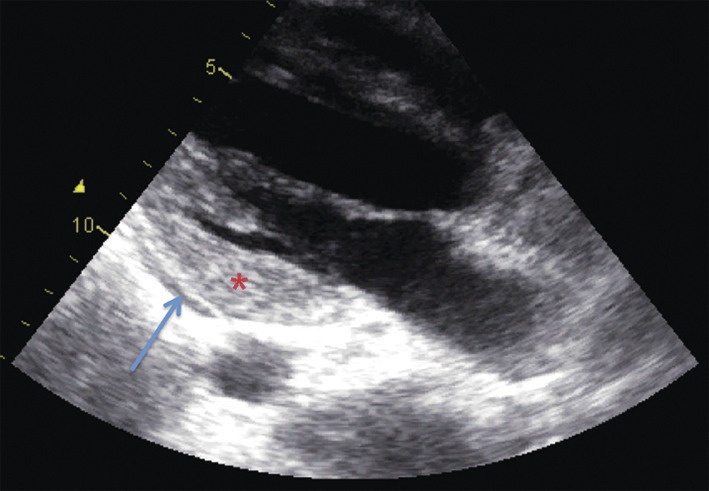

Le plus souvent, l’échocardiographie, indispensable à la prise en charge, est le premier examen réalisé (fig. 2). Elle oriente le diagnostic (troubles de la cinétique segmentaire, dilatation ventriculaire peu marquée, hypertrophie concentrique transitoire liée à un œdème pariétal, dysfonction ventriculaire droite, épanchement péricardique…). Elle contribue à la décision de biopsier et doit être répétée pour évaluer l’hémodynamique, la réponse au traitement et la récupération de la fonction cardiaque.